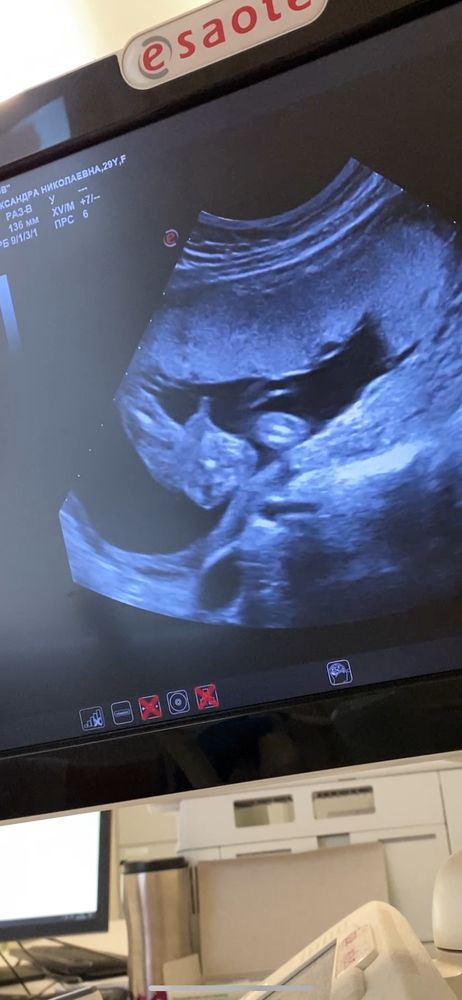

2 скрининг. 19 н 6 дней (завтра экватор)

ЭкваторС ума сойти, только вчера вроде увидела 2 полоски. А уже почти 20 недель и 2 скрининг позади!

У моей дочери будет младший братик.